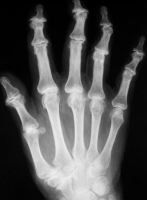

A osteoartrite, também conhecida como doença articular degenerativa, é um processo de deterioração progressiva da cartilagem articular e formação de osso novo (osteófitos) com a superfície articular. A osteoartrose primária está relacionada com a idade e associada a estresse mecânico. A osteoartrite secundária é devido a uma causa subjacente, como trauma, inflamatórias, metabólicas ou a doença do tecido conjuntivo. As características da doença são bem ilustradas nas mãos de adultos com osteoartrose nas figuras abaixo.